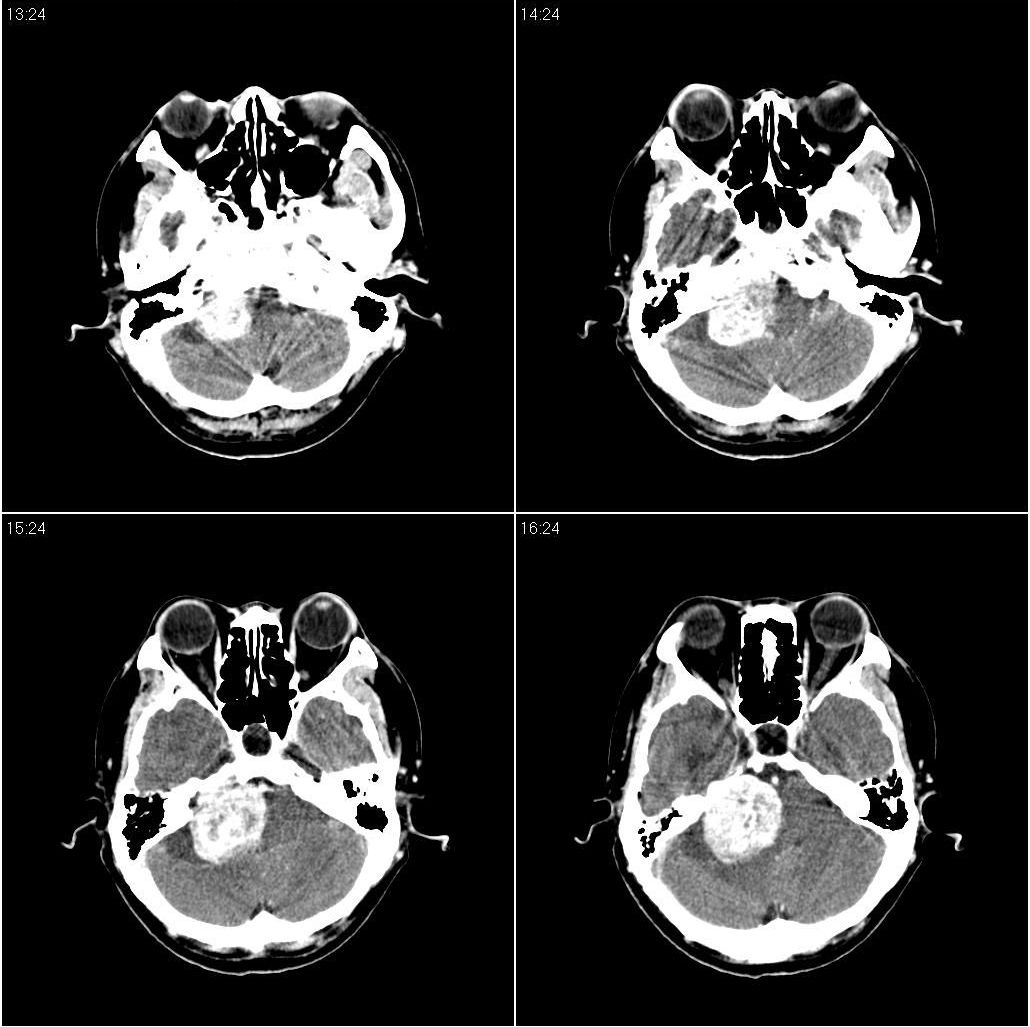

看到骨窗了,右侧内听道扩大(再往下扫一层),支持听神经瘤

现在有骨窗了,内听道口好像被开挖了一样,支持考虑听神经瘤先

右侧桥小脑角区占位性病变,内听道扩大,骨质似见破坏,考虑为听神经瘤

1)右侧听神经瘤。2)脑积水(梗阻性)。3)空蝶鞍。

支持右侧小脑半球占位性病变伴梗阻性脑积水。建议增强,上传骨窗,以听神经瘤可能大。

支持:1)右侧听神经瘤。2)脑积水(梗阻性)。3)空蝶鞍。